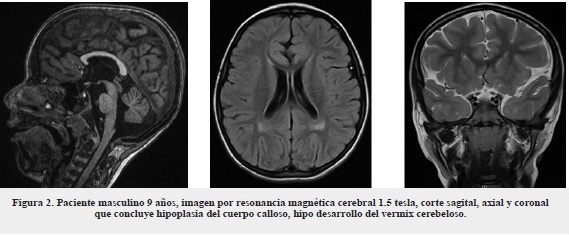

Paciente masculino de 9 años, con diagnóstico de epilepsia generalizada de inicio a los 5 años, refractaria a manejo farmacológico, con parálisis cerebral espástica y retraso neuromadurativo global. Antecedentes personales de infecciones respiratorias recurrentes, requirió hospitalización y manejo. Al examen físico con medidas antropométricas: talla 138 cm - peso 24 kg - PC 53 M - IMC 13 kg/M2. Fenotipo (figura 1) con paladar ojival, mallampathy III, implantación auricular baja, pabellón auricular proyectado hacia adelante, implantación baja del cabello, hipoplasia malar bilateral, escapulas aladas, genu varo, pie plano. Se realizaron paraclínicos (tabla 1) y resonancia magnética nuclear 1.5 tesla (figura 2), en la que se reporta hipoplasia del cuerpo calloso, hipodesarrollo del vermis cerebeloso.